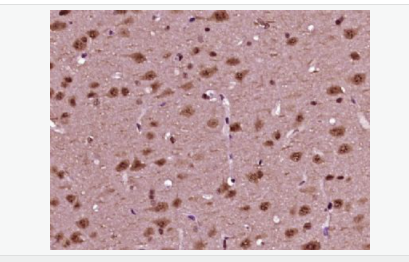

磷酸化神經細胞分化因子1抗體

Rabbit anti-phospho-NeuroD1 (Ser274) Polyclonal antibody

英文名稱phospho-NeuroD1 (Ser274)

中文名稱磷酸化神經細胞分化因子1抗體

別    名NeuroD1 (phospho S274); p-NeuroD1 (phospho S274); atonal; basic helix loop helix transcription factor; BETA 2; Beta cell E box transactivator 2; BETA2; BHF 1; BHF1; bHLHa3; class A basic helix loop helix protein 3; Class A basic helix-loop-helix protein 3; MODY 6; MODY6; NDF1_HUMAN; NEUROD; NeuroD1; Neurogenic differentiation 1; Neurogenic differentiation factor 1; neurogenic helix loop helix protein NEUROD; NIDDM.

產品類型磷酸化抗體

研究領域腫瘤  心血管  細胞生物  神經生物學  表觀遺傳學

產品應用WB=1:500-2000 ELISA=1:5000-10000 IHC-P=1:100-500 IHC-F=1:100-500 ICC=1:100-500 IF=1:100-500 (石蠟切片需做抗原修復)

分 子 量40kDa

細胞定位細胞核 細胞漿

免 疫 原KLH conjugated Synthesised acetylpeptide derived from human NeuroD1 around the acetylation site of Ser274:PL(p-S)PP

產品介紹This gene encodes a member of the NeuroD family of basic helix-loop-helix (bHLH) transcription factors. The protein forms heterodimers with other bHLH proteins and activates transcription of genes that contain a specific DNA sequence known as the E-box. It regulates expression of the insulin gene, and mutations in this gene result in type II diabetes mellitus. [provided by RefSeq, Jul 2008]

Differentiation factor required for dendrite morphogenesis and maintenance in the cerebellar cortex. Transcriptional activator. Binds to the insulin gene E-box.

Phosphorylated. In islet cells, phosphorylated on Ser-274 upon glucose stimulation; which may be required for nuclear localization. In activated neurons, phosphorylated on Ser-335; which promotes dendritic growth.

Defects in NEUROD1 are the cause of maturity-onset diabetes of the young type 6 (MODY6) [MIM:606394]. MODY is a form of diabetes that is characterized by an autosomal dominant mode of inheritance, onset in childhood or early adulthood (usually before 25 years of age), a primary defect in insulin secretion and frequent insulin-independence at the beginning of the disease.